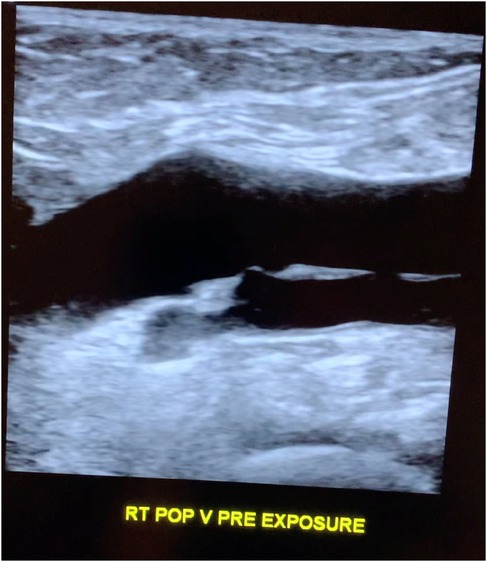

Hipoteza na wczesnym etapie opiera się na wynikach uzyskanych od zaledwie 1 pacjenta: 62-letniej kobiety, której żyły podkolanowe (duże naczynia krwionośne nogi) zostały zeskanowane przed i po 5-minutowej sesji trzymania różnych smartfonów z tyłu nogi, przy użyciu urządzenia ultradźwiękowego o tej samej "specyfikacji" i ustawieniach przez cały czas.

W badaniu wzięły udział tylko 2 urządzenia (z bardzo różnych roczników): iPhone XR iPhone XR i iPhone 16 Plus. Naukowcy stwierdzili, że badana osoba rzekomo wykazywała rouleaux w ruchomych grudkach w badaniu ultrasonograficznym po ekspozycji, w porównaniu do obrazów pokazujących, że jej żyły były całkowicie czyste na początku testu.